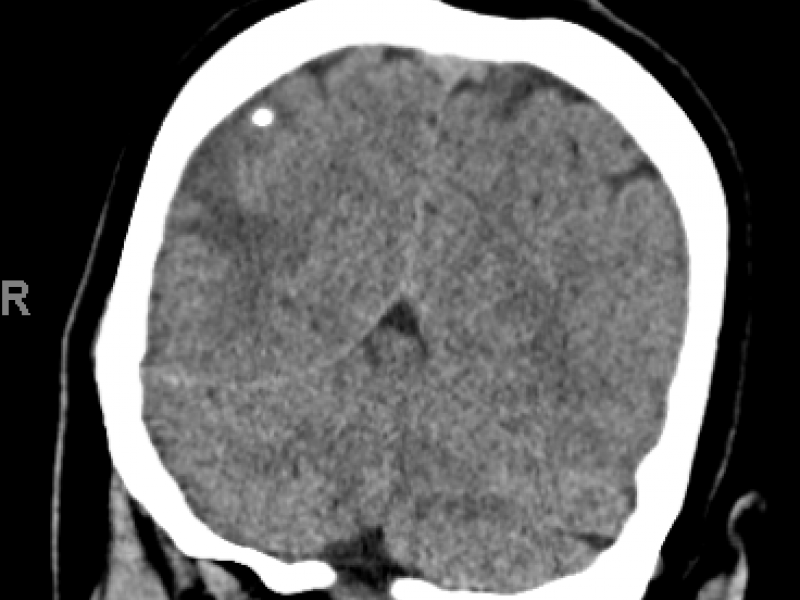

Imaging Case: Woman With Altered Mental Status

November 02 2016

Case: 55 year old female with unknown medical history